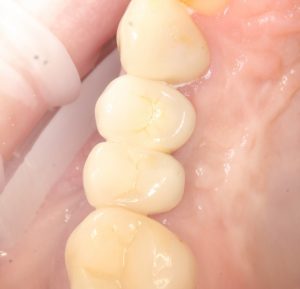

Поэтому после удаления зуба мы ждём, в общей сложности, около 4-8 недель, затем приступаем к имплантологическому лечению. Хотя, иногда бывают ситуации, когда мы делаем синуслифтинг одномоментно с удалением зуба, а сам имплантат ставим попозже:

через 4 месяца: